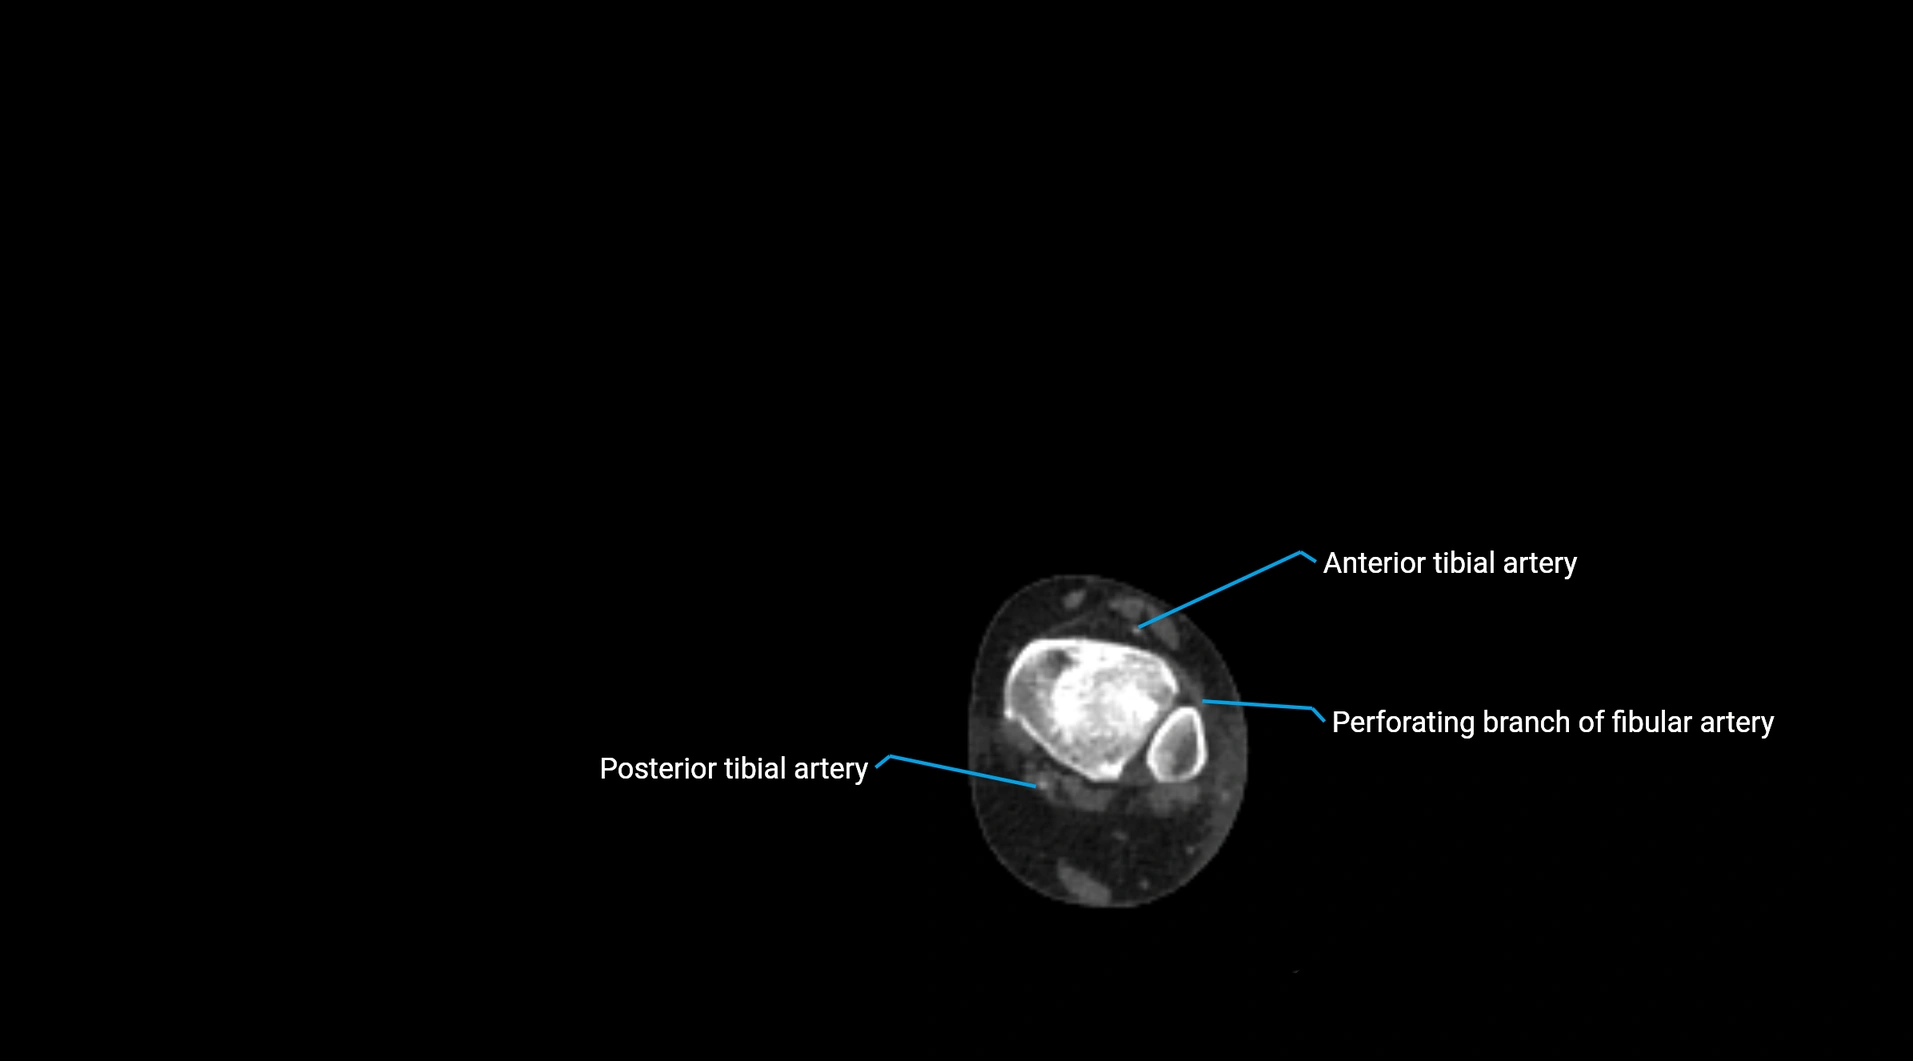

Contrast-enhanced CT (CTA):

• Gold standard for abdominal aortic imaging

• Provides excellent detail of lumen, wall, aneurysm, thrombus, and branch vessels

• Multiplanar and 3D reconstructions help in aneurysm measurement, stent graft planning, and dissection evaluation

• Detects acute rupture, traumatic injury, or occlusion with high sensitivity